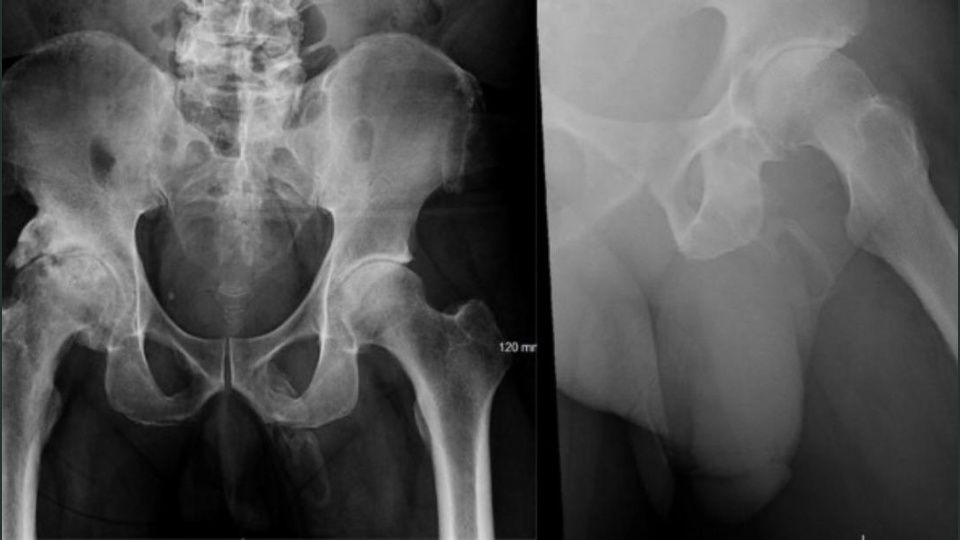

Al realizarle una radiografía para verificar que no se había roto la cadera mostró tejido óseo formándose en su pene.

Mientras lo revisaban, los médicos le tomaron una radiografía de la pelvis para verificar que no había huesos rotos, pero encontraron algo más extraño de lo que esperaban.

Lo diagnosticaron con una osificación, lo que significa que una parte del cuerpo se convierte lentamente en hueso.

En un informe de caso, los médicos, dirigidos por Georges El Hasbani de la Universidad Americana de Beirut, dijeron que la afección es "extremadamente rara". La osificación del pene sigue siendo una condición relativamente rara que se menciona en muy pocas revistas, con menos de 40 informes de casos publicados